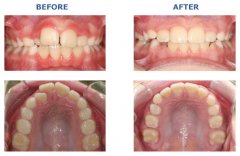

牙齿不齐怎么矫正?

看到明星一口整齐靓丽的牙齿,是否羡慕不已。随着现代医疗技术的进步,牙齿...【详细】